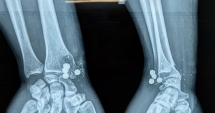

Nam thanh niên nghịch súng kíp, 5 viên đạn nổ găm vào cổ tay

Nam thanh niên đến nhà bạn chơi, thấy khẩu súng kíp gác trên mái nhà đưa xuống xem. Trong lúc nghịch súng, bất ngờ súng nổ, 5 viên đạn bắn thẳng vào cổ tay phải ...